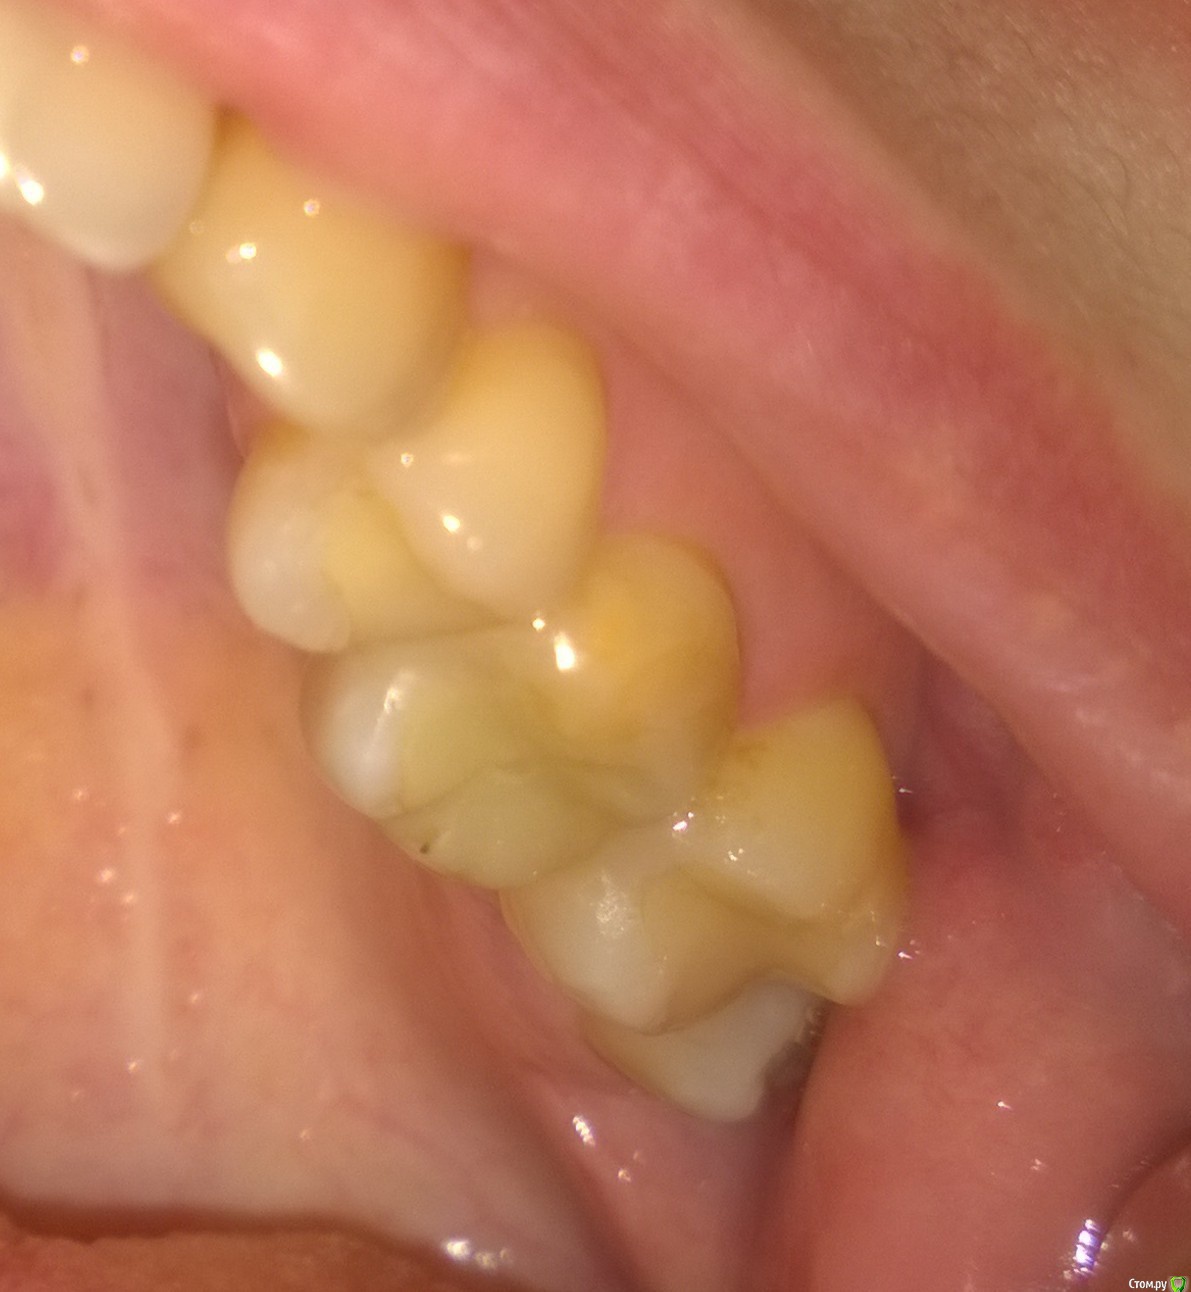

Fenya Опубликовано 12 апреля, 2016 Поделиться Опубликовано 12 апреля, 2016 Добрый вечер, уважаемые специалисты! Помогите пожалуйста определиться с планом лечения! Разболелся 6-ой верхний зуб, посетила две стоматологии - в первой однозначно сказали удалять и через месяца 4 задуматься об имплантации; во второй предложили три варианта на выбор: 1. удаление и постановка моста без удаления нервов зубов; 2. можно попробовать полечить, если очень хочется, но естественно гарантий вообще никаких; 3. ну и удаление с последующей операцией по восстановлению кости и имплантация. Врач сказал, что киста большая, если удалять зуб, то очень осторожно, т.к. здоровой кости очень мало и можно ее сломать (пишу на своем обывательском языке - как поняла, простите, если допускаю терминологические ошибки ). Врач предпочитает первый вариант развития событий, т.к. неблагоприятная ситуация для имплантации, а лечение может поможет, а может и нет... Ну и вопрос: Может попытаться полечить? Я же вроде ничего не теряю, кроме времени и денег, в случае неблагоприятного исхода? Или все-таки могу усугубить ситуацию со здоровьем пытаясь продлить жизнь зубу? Мостов патологически боюсь, собственно как и имплантов (установила на единичке имплант два месяца назад - до сих пор беспокоит, хотя по внешним признакам врач говорит все отлично, да и по отзывам других пациентов должна была о нем давно забыть). Ссылка на комментарий

Fenya Опубликовано 21 апреля, 2016 Автор Поделиться Опубликовано 21 апреля, 2016 Вы бы показали нам КТ и Все снимки которые есть, возможно мнение изменилось бы.По факту есть воспалительный процесс ( киста или нет это еще неизвестно) который затрагивает дно пазухи. И требуется устранение источника инфекции внутри зуба либо зуба целиком. Такие скрины подходят или выложить все КТ? Если все, то подскажите, какие файлы выложить в файлообменник? Ссылка на комментарий